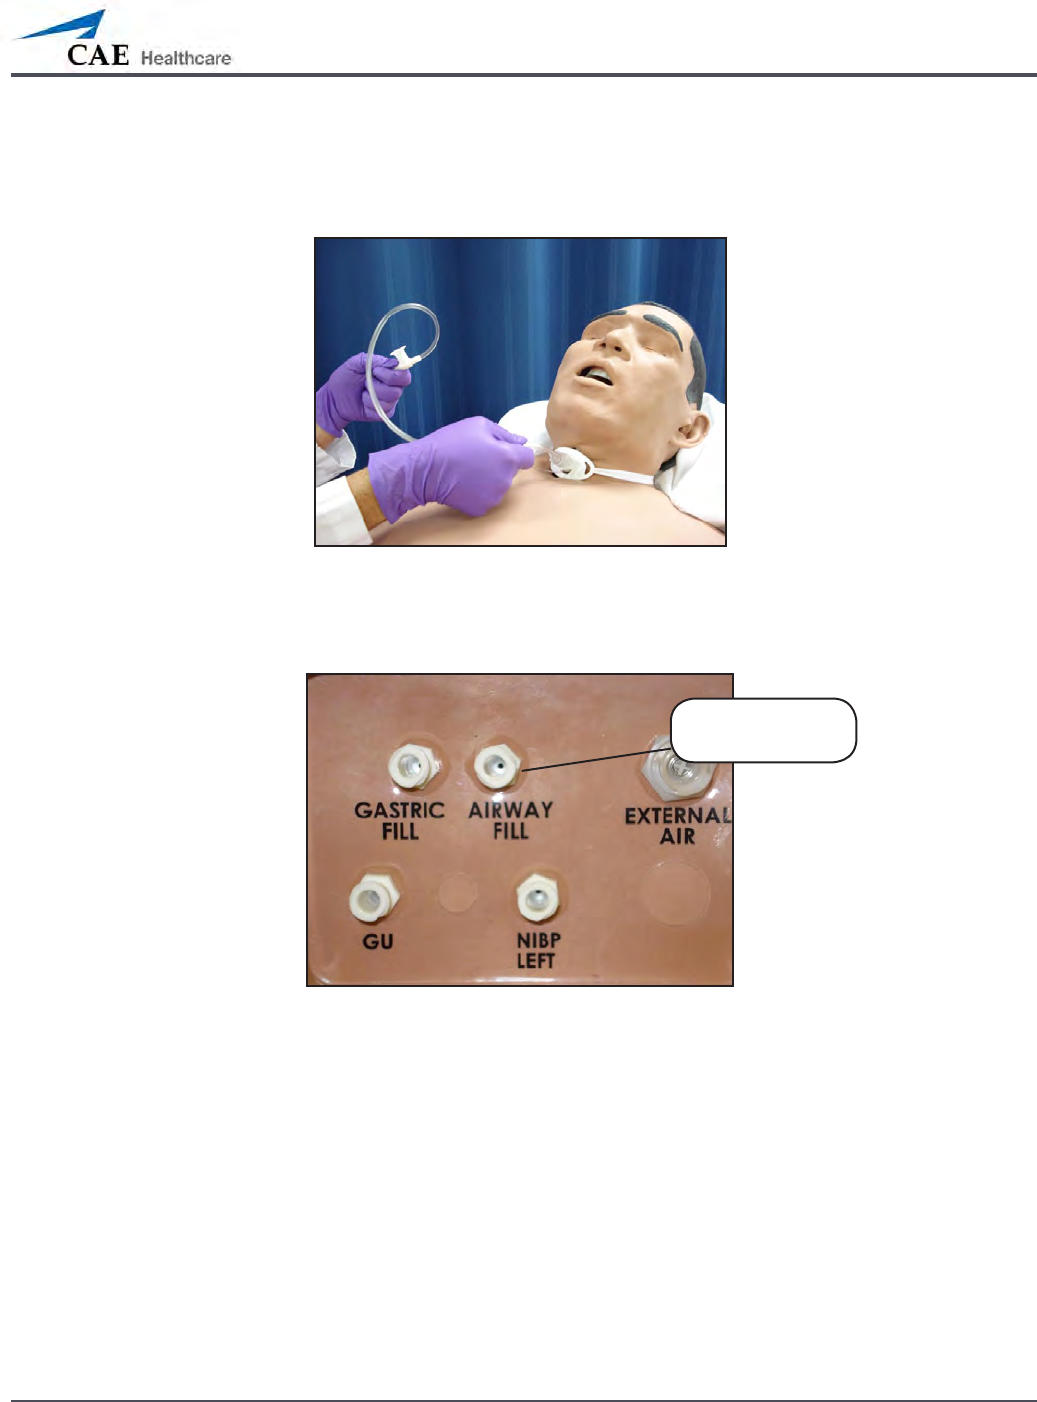

Airway Secretions (Nursing Only)

METIman Nursing allows for suctioning of uids from the airway using a manual feed. Ensure

all uids have been removed from previous uses before each new use to prevent overlling.

Tracheostomy Suction

To use the airway secretion feature, inject up to 40 mL of clinically appropriate colored uid

into the AIRWAY FILL port on METIman Nursing’s left shoulder.

METIman Nursing’s Left Shoulder

The trachea is now ready to be suctioned. Using the proper clinical technique, insert the

suction catheter (14 Fr) until resistance is encountered at the bifurcation. Withdraw and apply

suction. Fluid can be suctioned over a distance of approximately 4 cm distal to the bifurcation.

NOTE: Use only distilled water with food coloring, if desired.

NOTE: Cleanup is very important when using simulated uids. Please refer to the Care and

Maintenance section for directions on uid removal.

The AIRWAY

FILL port

136